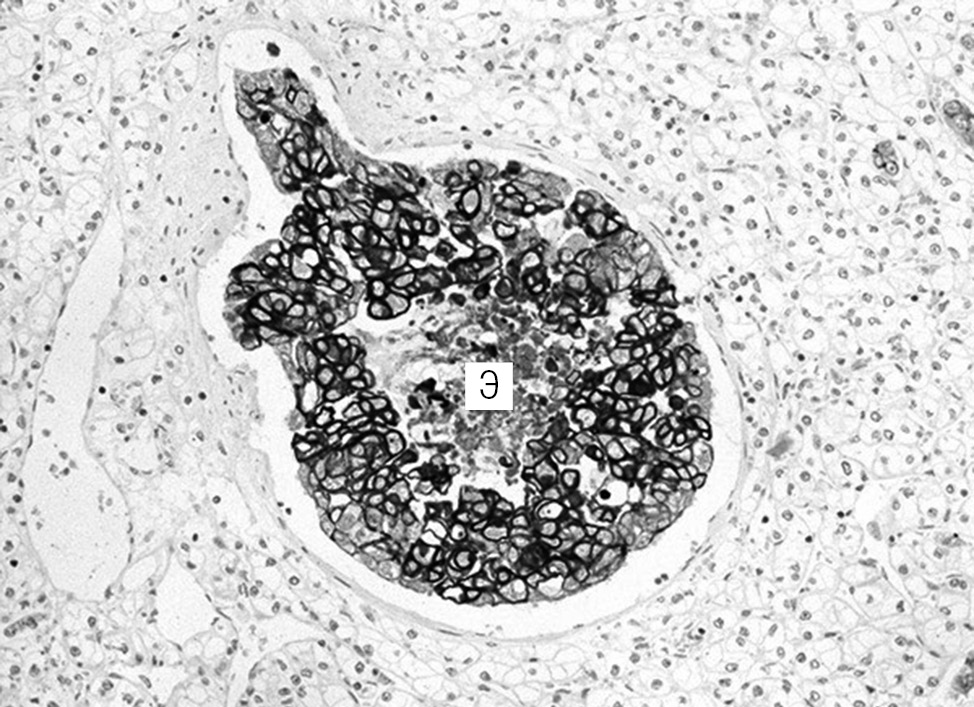

Aim of the study is to demonstrate a unique case report: synchronous malignant tumors of the breast and kidney with tumor to tumor metastasis.

Materials and methods. The analysis of medical history and the pathology study of surgical material using histological and immunohistochemical methods was carried out.

Results. Clinical observation of metastasis of triple-negative breast cancer in a synchronous renal cell carcinoma of the kidney in a 59-year-old woman has been described. Tumor to tumor metastases are diagnosed by a remote kidney with a neoplasm, hematuria, anemia, and thrombocytopenic syndrome manifested in the clinic.